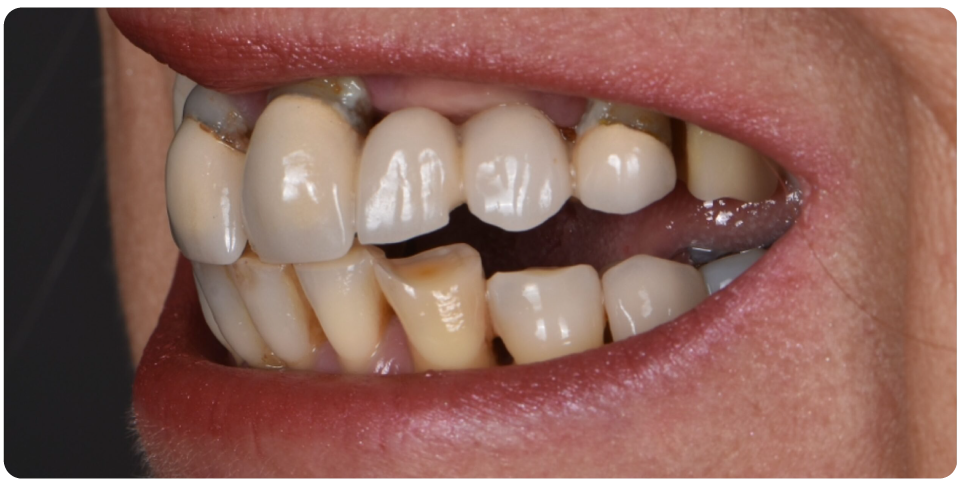

Complex Implant Rehabilitation

Complex dental implant rehabilitation is a highly effective solution for patients with extensive dental issues.

Such as severe bone loss, multiple missing teeth, cases involving tumor resection and reconstruction with vasculised bone grafts, gun shot injuries, with cleft lip and palate, jaw necrosis, post cancer oral rehabilitation.

Treatment plan includes Detailed clinical and radiographic evaluation of the patient’s general and oral health, including gum condition, remaining teeth, and bone structure with 3D scans, X-rays, and CT scans.